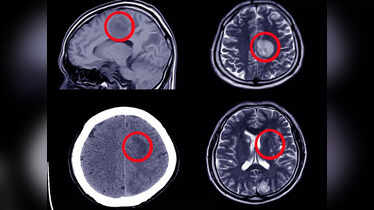

12 Anzeichen für ein Hirnaneurysma – ignorieren Sie sie nicht

Ein Hirnaneurysma ist eine stille, aber potenziell tödliche Erkrankung, die ohne Vorwarnung auftreten kann. Es entsteht, wenn ein Blutgefäß im…